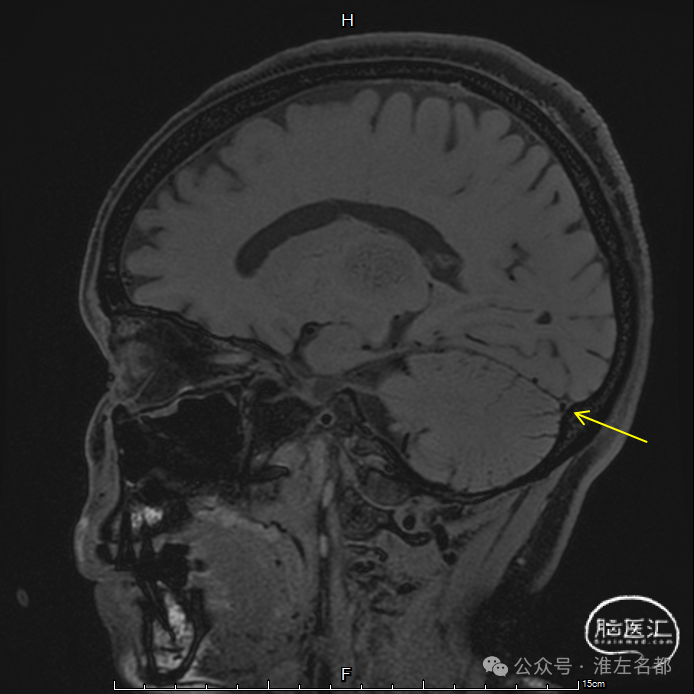

三维黑血高分辨T1

三维黑血高分辨T1平扫(上图)和增强(下图):右侧乙状窦慢性血栓,平扫呈等低信号,并显著强化。

三维黑血高分辨T1平扫(上图)和增强(下图):右侧横窦慢性血栓。

三维黑血高分辨T1平扫(上图)和增强(下图):上矢状窦慢性血栓;直窦内新进血栓(急性血栓等低信号,或亚急性血栓高信号,无强化)。